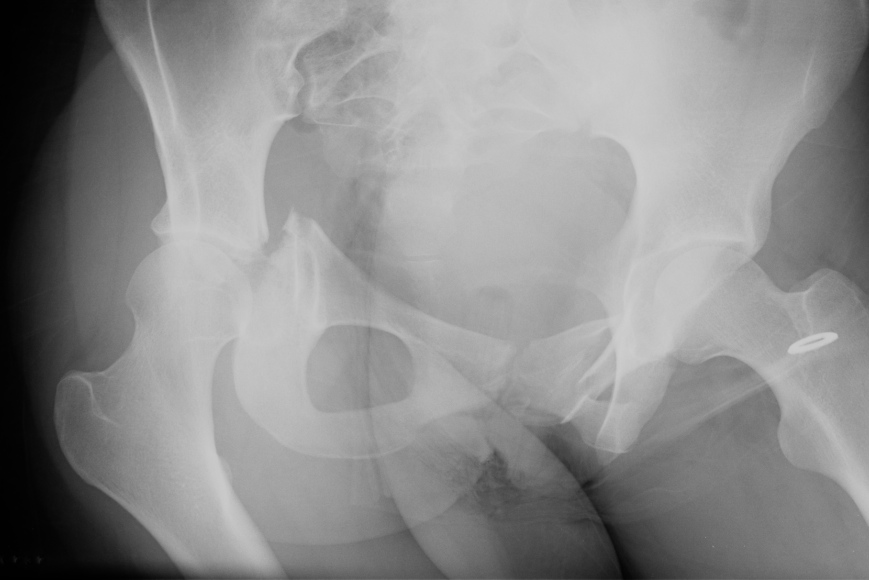

X-ray / 5 standard views

AP / Six X-ray Landmarks

1. Iliopectineal line

- along pelvic brim to pubic symphysis

- anterior column

2. Ilioischial Line

- pelvic brim to ischial tuberosity

- posterior column

- formed by posterior 4/5 of quadrilateral surface ilium

3. The Teardrop

- lateral: subchondral bone condensation at anterior margin of cotyloid fossa

- medial: anterior flat part of quadrilateral surface of iliac bone

4. Roof of acetabulum

5. Anterior rim of acetabulum

- semilunar

6. Post rim of acetabulum